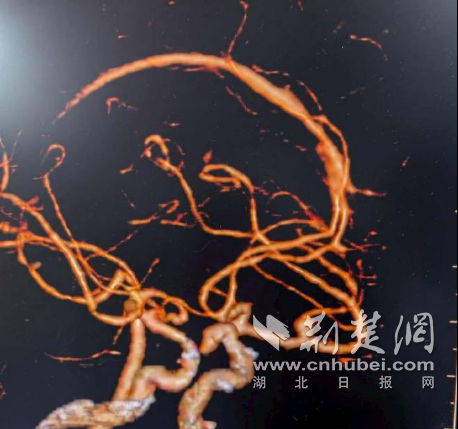

- 中西医结合双镜夹攻巧切“葫芦瘤”

- 十堰市中西医结合医院胸脑外科团队精准介入治疗成功挽救危重患者生命